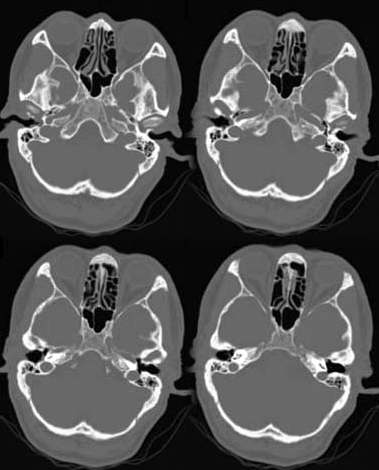

患者自述小时候左耳听力下降,现在右耳听力亦有下降,经医生治疗,说曾掏出胆脂瘤样物,请大家会诊.

双侧乳突蜂房气化不良,鼓窦、蜂房密度稍增高,右侧较左侧明显,未见骨质破坏。考虑双侧慢性中耳乳突炎。

蜂房气化不良,支持双侧中耳乳突炎,胆质瘤是由中耳乳突炎发展而成,故不除外该病变可能。

右侧的听骨链好象不正常,其他支持乳突炎

支持双侧慢性中耳乳突炎。另外有径静脉球高位

双侧乳突气化不良,密度稍高,右侧鼓室内见软组织影,双侧听骨链显示不完整。考虑乳突炎,听骨链发育异常。

影像:右侧外耳道内可见一低水样密度影,双侧乳突气房消失,密度增高,内耳道显示清楚,未见明显异常。

诊断:双侧慢性乳突炎,右侧外耳道积液或囊肿可能。

双侧乳突小房气化欠佳,同时壁骨质密度增高,左侧显著。考虑为双侧慢性乳突炎。